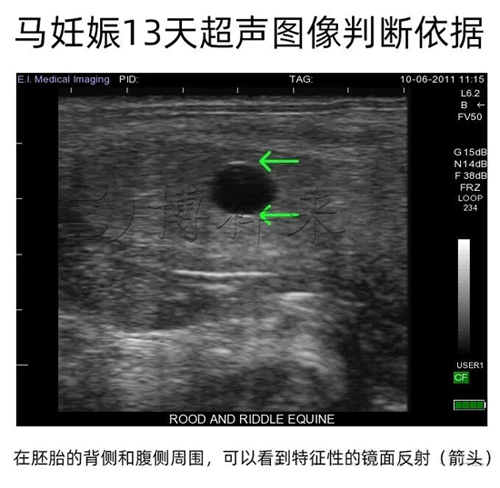

在早期超声影像中,正常胚囊常有一个很典型的镜面反射:在囊胚的背侧和腹侧可能出现两道明亮的回声线。这是因为球形界面产生的回声增强,反而是识别怀孕与区别不规则子宫囊肿的有用线索。

若见到镜面反射(双侧明亮回声线),优先考虑胚囊,而非不规则的子宫囊肿;

与子宫囊肿鉴别:囊肿通常边缘不规则、形态多样;球形胚囊伴镜面反射更支持妊娠诊断。